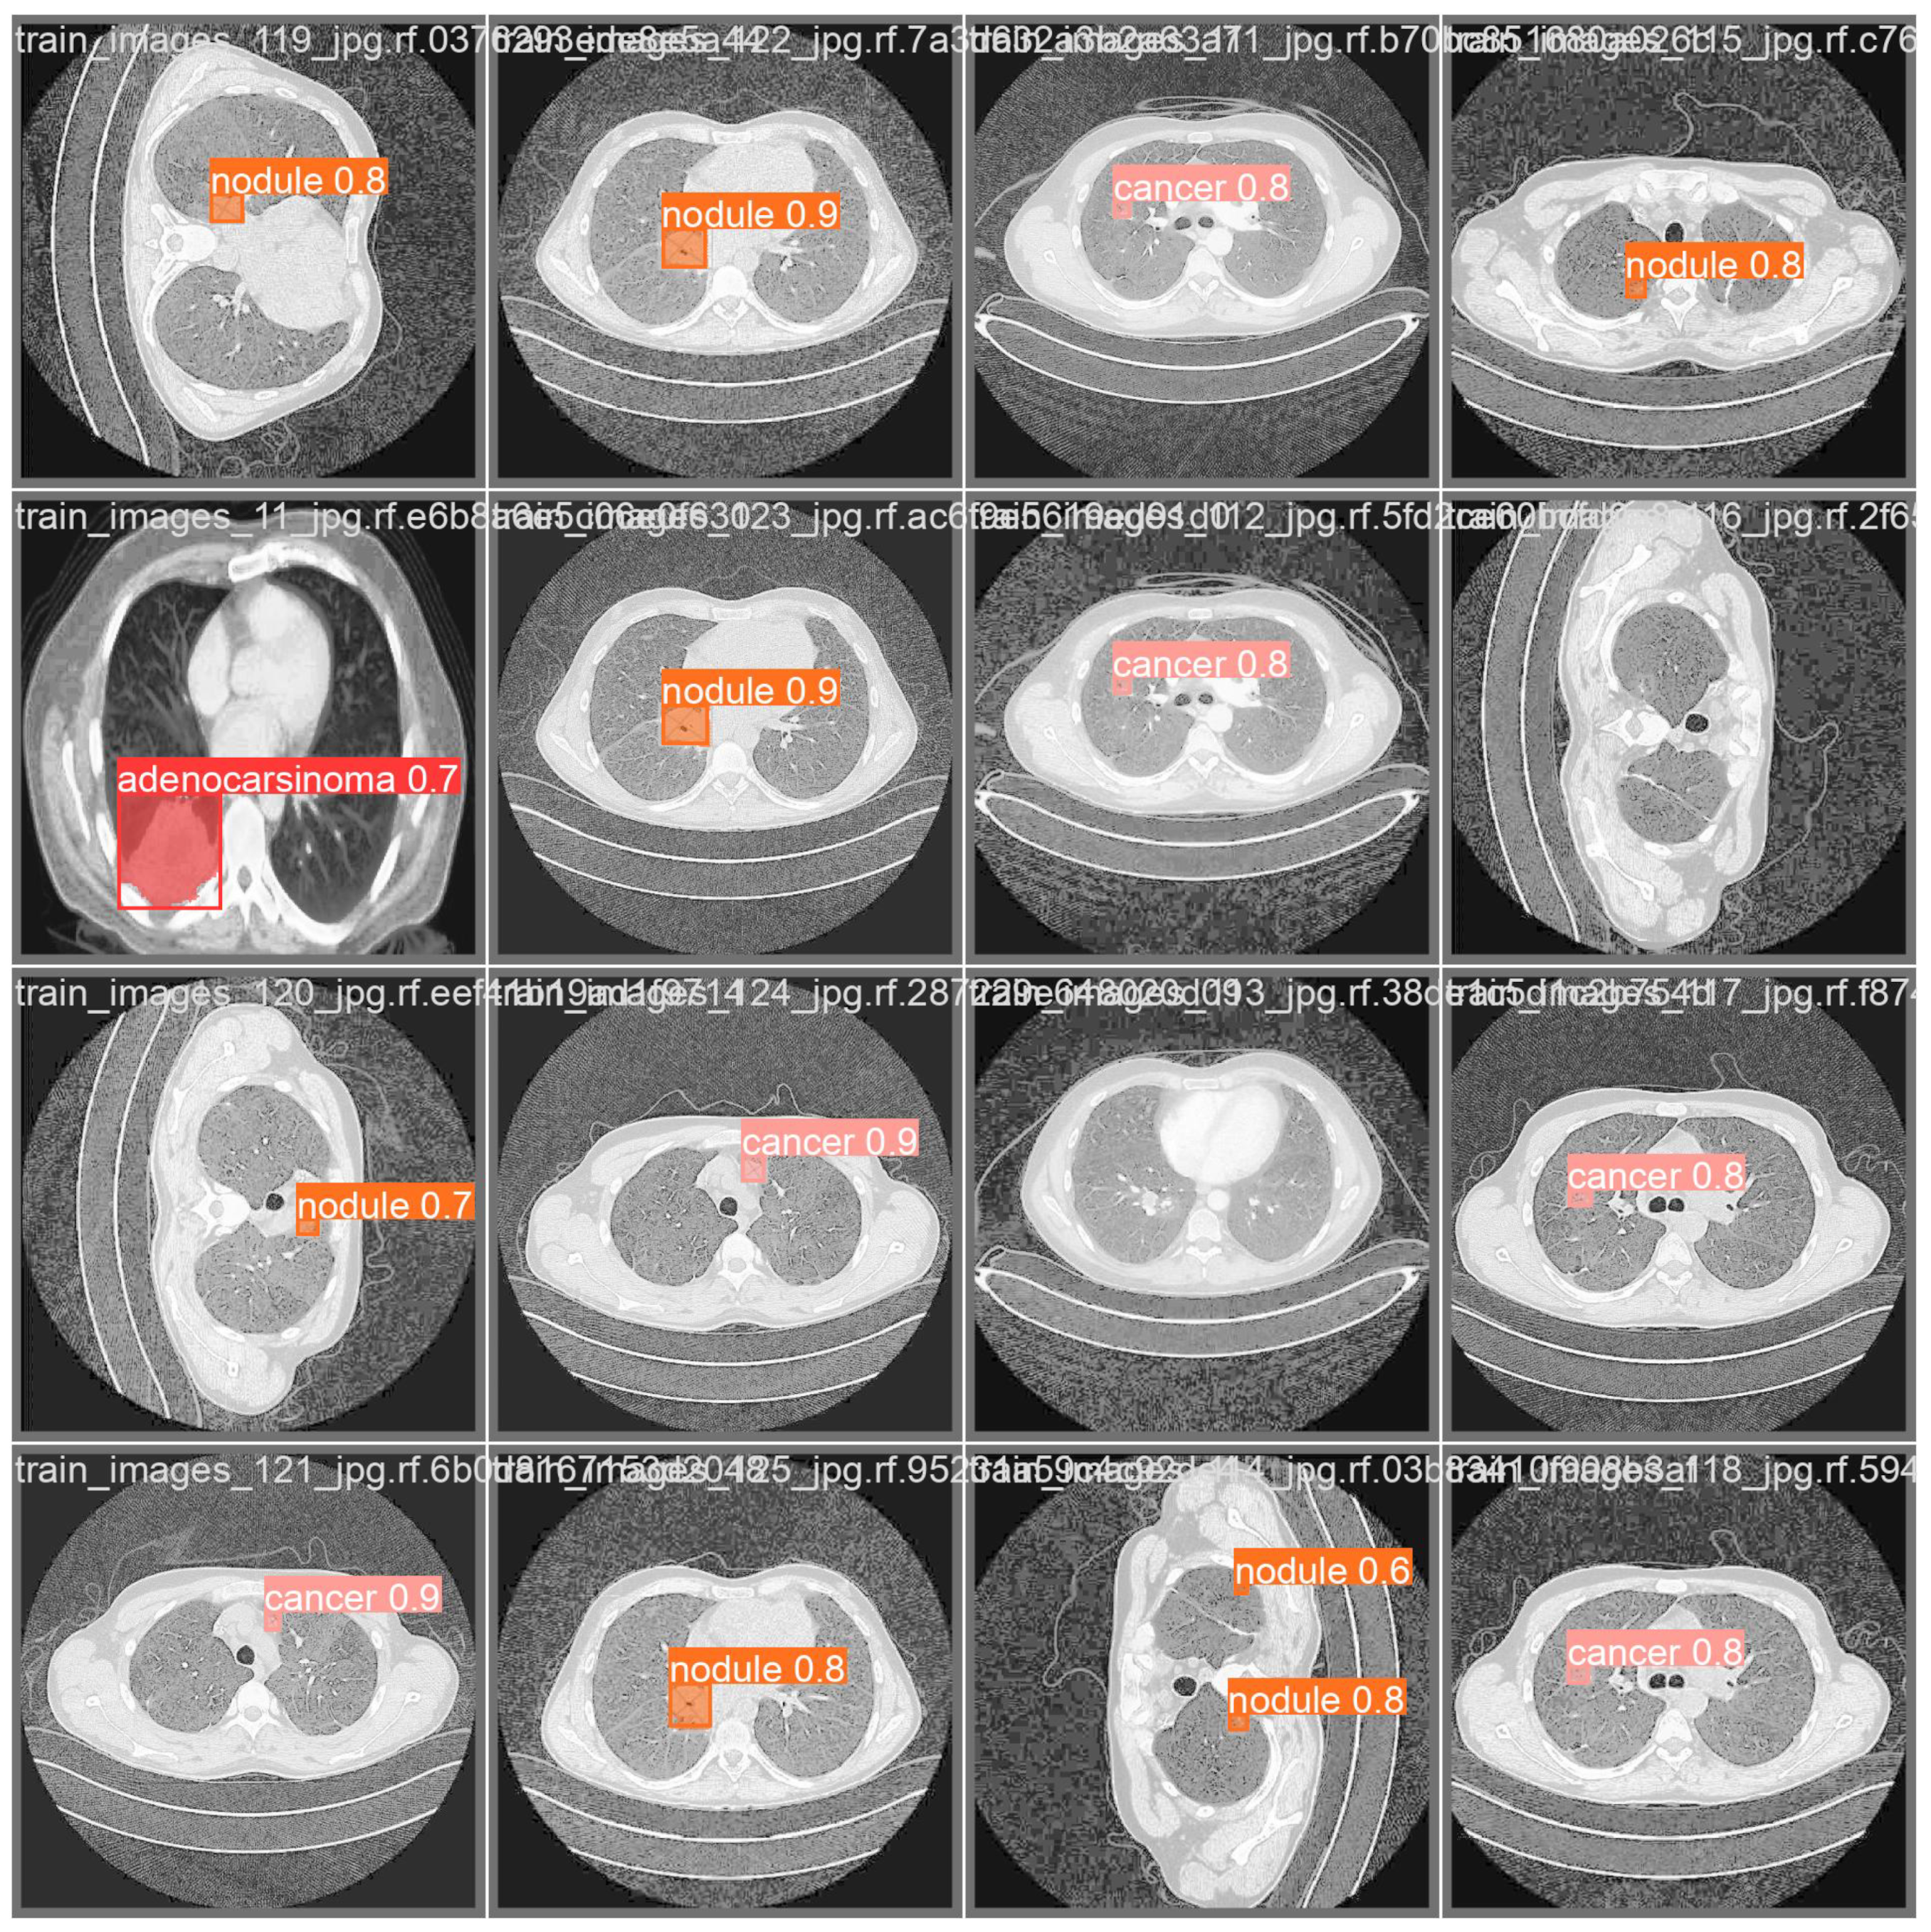

- Adenocarcinoma (Blue Line):

- -

- The blue line represents the precision–recall relationship for the adenocarcinoma class.

- With an average precision (AP) of 0.734, the model performs relatively well in detecting adenocarcinoma, maintaining high precision and recall values.

- Cancer (Orange Line):

- The orange line represents the performance for the cancer class.

- An AP of 0.588 indicates moderate performance, with a noticeable drop in precision as recall increases, suggesting that the model struggles more with this class compared to adenocarcinoma and nodules.

- Nodule (Green Line):

- The green line shows the precision–recall for nodules.

- With the highest AP of 0.802, the model performs best on this class, indicating high precision and recall across most thresholds.

- All Classes (Bold Blue Line):

- The bold blue line represents the overall performance across all classes, with an mAP@0.5 of 0.708.

- The mean average precision (mAP) at an IoU threshold of 0.5 provides a single metric summarizing the model’s performance across all classes.

- An mAP@0.5 of 0.708 suggests that the model has a strong overall detection capability, balancing precision and recall well.

| Class | Image | Instances | Box (P) | Box (R) | Box (mAP50) | Box (mAP50-95) |

|---|---|---|---|---|---|---|

| all | 324 | 332 | 0.757 | 0.738 | 0.71 | 0.488 |

| adenocarsinoma | 324 | 45 | 0.815 | 0.685 | 0.713 | 0.492 |

| cancer | 324 | 46 | 0.572 | 0.783 | 0.588 | 0.467 |

| nodule | 324 | 241 | 0.884 | 0.747 | 0.831 | 0.505 |

| Class | Image | Instances | M (P) | M (R) | M (mAP50) | M (mAP50-95) |

| all | 324 | 332 | 0.75 | 0.733 | 0.708 | 0.438 |

| adenocarsinoma | 324 | 45 | 0.815 | 0.685 | 0.734 | 0.539 |

| cancer | 324 | 46 | 0.572 | 0.783 | 0.588 | 0.366 |

| nodule | 324 | 241 | 0.865 | 0.73 | 0.802 | 0.41 |